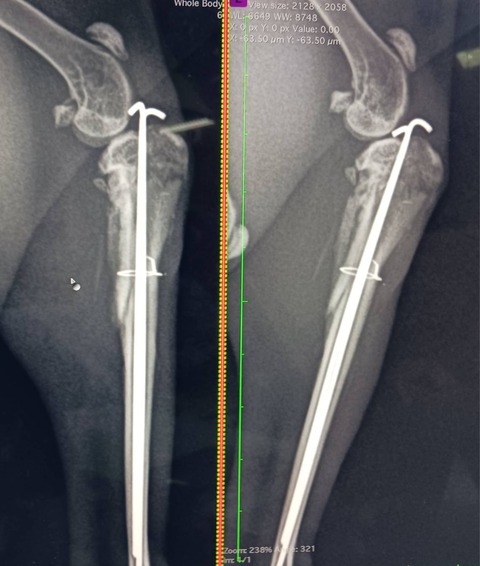

2025年11月に右後ろ脚を骨折し、11/14にピンニング手術を受け、現在も経過観察中です。

12/5 経過を見るために受診しました。

骨の再生がほとんど見られず、経過は想定より厳しい状況との説明を受けました。

後方2か所にわずかな骨量の増加は見られるものの、2か月経過しても反応が乏しい場合は、ピンを留置したままの経過観察、再手術、または断脚も選択肢になるとのことでした。

右後肢は力が入りにくいものの、痛みの反応はあり、神経は保たれている可能性が高いとの見立てでした。

今後は足を使う機会を増やし、2〜3週間後に再度レントゲンで確認する予定となりました。

12/19 経過を見るために受診しました。

骨の再生が少しずつ進んでいることが確認できました。

左かかとにソアホックはなく、右後肢の筋肉量は落ちているものの、前回と比べ大きな悪化は見られませんでした。

足を浮かせる原因については、ピン挿入による違和感や、受傷時の筋肉・神経・靭帯への影響などが考えられるものの、判断は難しいとのことでした。